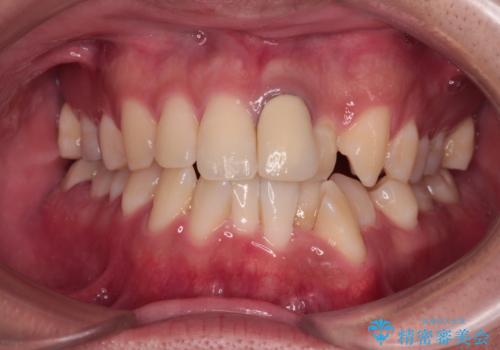

口が閉じにくい 1本飛び出した前歯の矯正治療

- 1本飛び出した前歯を治したいとのことで来院された患者様です。

歯列全体の拡大とIPR(歯と歯の間を削る)によってデコボコが解消するようにし、さらにゴムかけを活用して右側の咬み合わせ位置を変えるように設計し、インビザラインにより治療を行うこととしました。